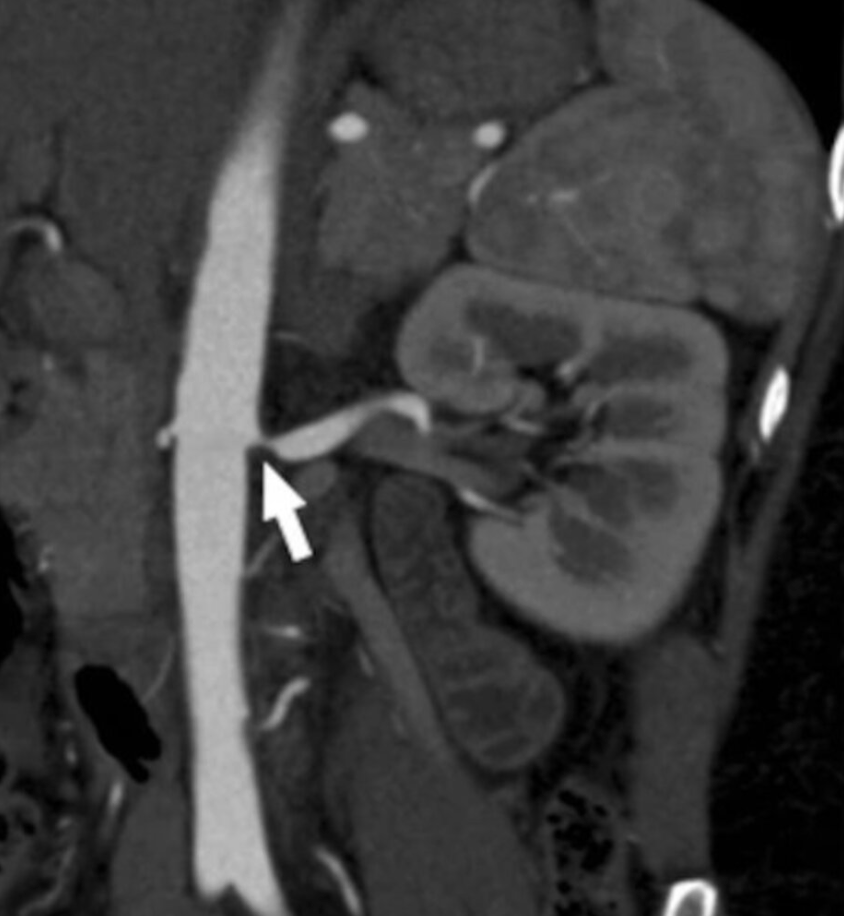

RAS Imaging: CT Angiography

Fibromuscular dysplasia